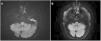

The patient was a 66-year-old man who consulted due to 4 days’ progression of instability and oculomotor alterations, of sudden onset. The examination revealed bilateral adduction impairment, contralateral abduction nystagmus, and primary gaze exotropia, with preserved convergence. Due to suspicion of acute bilateral internuclear ophthalmoplegia, the patient was admitted for further study. An MRI study (Fig. 1) revealed a lacunar infarction in the lower paramedian pons; the patient received dual antiplatelet therapy and was discharged.

Seven days later he consulted due to bilateral peripheral facial paralysis and dysarthria. The physical examination revealed facial diplegia and bilateral Bell’s phenomenon (Fig. 2), as well as WEBINO syndrome, without involvement of other cranial nerves or paresis of the limbs; deep tendon reflexes were preserved. Blood tests (autoimmunity, serology, and total protein tests), CSF analysis (no albuminocytologic dissociation), and electroneurography of the limbs yielded normal results. The blink reflex revealed axonal neuropathy of both facial nerves, with involvement of the trigeminofacial reflex arc. A subsequent MRI study (Fig. 1) revealed decreased signal intensity of the paramedian pontine stroke on T2-FLAIR and DWI sequences, linked to the subacute progression of the infarction.